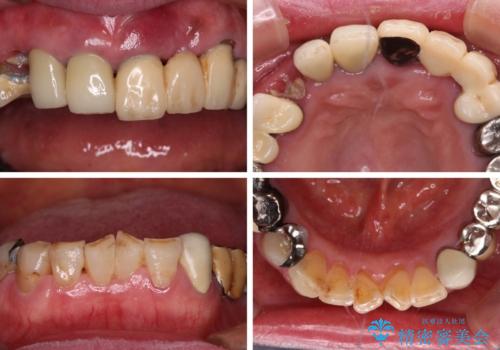

- 抜歯の必要な前歯や、以前治療した前歯のクラウンの外観を気にして来院された患者様です。

上顎犬歯や下顎大臼歯は、必要なところはインプラントを埋入することとしました。

クラウンが不適合であったり、根管治療の必要なほどの痛みのある歯であったり、見た目の気になる前歯などをオールセラミッククラウンに補綴治療を行うこととしました。